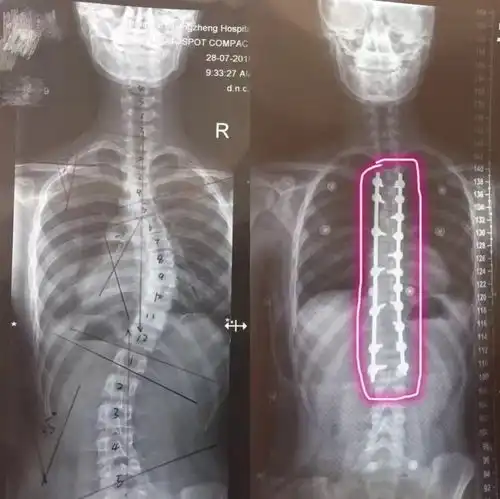

12岁安徽男孩脊柱畸形十年,终于在这挺直了腰